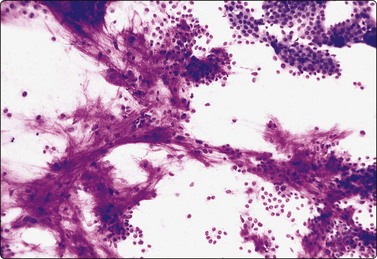

Fig. 4.25 Chronic sialadenitis

Fragments of epithelium mainly of ductal origin showing mild reactive atypia and some squamous metaplasia; fragments of fibrous stroma; relatively few chronic inflammatory cells. (A, MGG, IP; (B, Pap, IP).

image image

Fig. 4.26 Chronic sialadenitis

(A) Sheet of ductal epithelium showing squamous metaplasia. This could be mistaken for low-grade mucoepidermoid carcinoma or other low-grade neoplasm (Pap, HP); (B) Corresponding histology, most acinar epithelium replaced by fibrous tissue with patchy inflammatory cell infiltration, and prominent ducts showing mild reactive atypia and squamous metaplasia (H&E, IP).

Criteria for diagnosis

Purulent aspirate in acute, infective sialadenitis,

Scanty material of mainly ductal epithelial cells, few acinar cells in chronic sialadenitis,

Sheets of ductal epithelium showing regenerative atypia and/or squamous metaplasia,

Variable numbers of inflammatory cells, usually few in chronic sialadenitis,

Fragments of fibrous stroma.

Purulent material aspirated from a tender, swollen gland suggests infective sialadenitis. Smears contain a mixed population of numerous neutrophils, foamy degenerate cells and endothelial cells. The swelling should subside after antiinflammatory treatment.

Most cases of chronic sialadenitis referred for FNB are in a late stage when interstitial fibrosis and atrophy of acinar tissue have taken place. The inflammatory cell infiltration may have subsided and may be sparse and patchy. FNB smears are therefore often scanty, mainly of ductal epithelial cells associated with only few acinar cells and inconspicuous inflammatory cells. Fragments of fibrous stroma are often present (Fig. 4.25). Crystalloids may be present in the aspirate.95 Regenerating ductal epithelium in chronic sialadenitis may undergo squamous metaplasia and may appear atypical (Fig. 4.26). Mucus-like material from dilated ducts may be present. This may be suggestive of a neoplastic lesion or even of malignancy, mainly low-grade mucoepidermoid tumor. Multiple sampling and clinical correlation usually solves the problem.